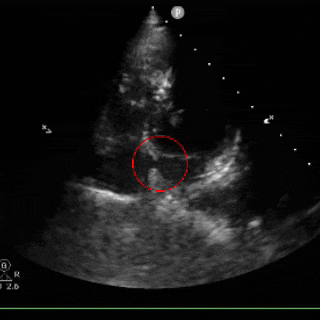

经胸右心声学造影:静息状态下,左侧肘静脉注射激活生理盐水(10ml),右心显影后,左心内未见明显微气泡,行Valsalva动作后右房增压状态,注射激活生理盐水(10ml),5秒后右心显影,左心内即刻出现10-15颗微气泡。

术后心超随访:心脏各房室结构及室壁厚度正常,室壁运动协调,升主动脉及肺动脉内径无异常;房间隔封堵器位置稳定,CDFI证实心房水平未见残余分流。各瓣膜形态及启闭功能正常,未探及明显反流。

各房室腔内径正常范围:房间隔可见封堵器强回声,位置固定;室间隔与左室后壁不厚,呈逆向运动,运动幅度正常;升主动脉内径正常,主肺动脉内径不宽。各瓣膜形态回声正常;

CDFI:房水平未见明显分流信号。心尖四腔心切面流入道呈红色血流束,流出道呈蓝色血流束;频诺多普勒显示,各瓣口均呈层流频谱。

卵圆孔未闭封堵术后

目前心内结构及功能未见明显异常